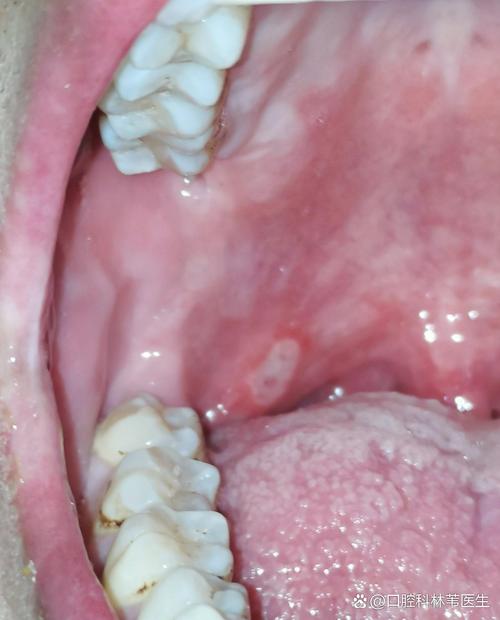

口腔上颚粘东西是何原因?

下面我为您详细分析一下可能的原因、伴随症状以及相应的解决方法。(图片来源网络,侵删) 可能的原因 生理性/生活习惯性原因(最常见) 口腔干燥(唾液分泌减少):这是最常见的原因,唾液有清洁和润滑口腔的作用,当唾液分泌不足时,口腔黏膜会变得干燥,食物残渣、脱落的细胞和细菌就容易附着在上颚,形成“粘粘”的...